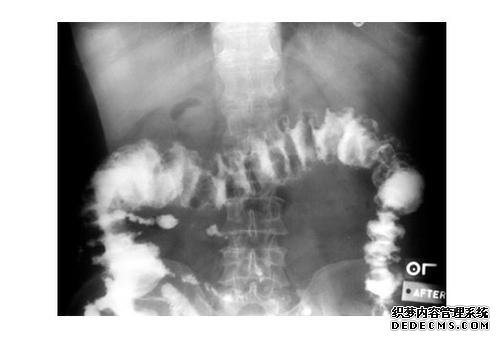

使用钡灌肠,将稀释的tin剂通过肛门注射,然后使用少量气体使直肠,整个结肠和盲肠发育。

包括简单的钡剂灌肠和气体双对比血管造影。

第一个仅用于评估阻塞和骨患者。后者是最常用的结直肠X射线检查,可以通过观察粘膜症状,占位的几个结肠病变(结直肠癌),炎性病变,憩室来检测小病变可用于测试肠道疾病,肠套叠和先天性大结肠等疾病。